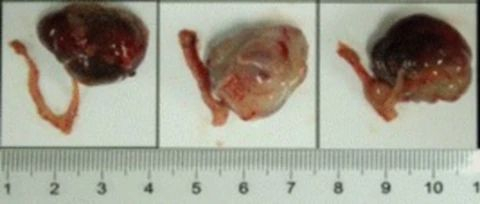

ʹÓó¬Éù¶àÆÕÀպͳ¬Éù»Ø²¨ÔÀí£¬£¬£¬£¬¿ÉÒÔÏÔʾ³ö¾Ö²¿ÓÐʵÖÊÐÔµÄÖ×Áö£¬£¬£¬£¬ÌØÊâÊÊÓÃÓÚÉöÔà¡¢ÒÈÏÙ¡¢Âѳ²¡¢°òë׵Ȳ¿Î»µÄÔλÖ×ÁöÄ£×Ó¼à²â¡£¡£¡£